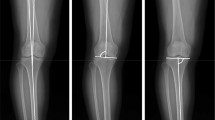

This retrospective study included 1036 non-consecutive patients (872 lower extremities; 456 male and 580 female patients) with end-stage knee OA (Kellgren-Lawrence [18] grades 3 and 4) who underwent TKA (Fig. 1). The study period was between March 2006 and December 2019. The average age at the time of surgery was 73 ± 8 years. The inclusion criteria were a medial compartment affected by end-stage OA with varus deformity. The exclusion criteria were lateral compartment OA, OA with valgus alignment, post-traumatic OA, rheumatic arthritis including other inflammatory arthritis types, and a post-infection state. Patients with flexion contracture greater than 10° were also excluded from the study as their inclusion could result in altered reciprocal rotational position between the femur and tibia [1]. All patients underwent preoperative standing full-limb anteroposterior (AP) radiography and lower extremity axial CT. The demographics and past medical histories of the patients were evaluated by reviewing their medical records (Table 1).

The coronal alignment of the lower extremity was measured using standing AP radiography of the lower extremities. Digital radiography was performed using the DGR-C54J2B (Samsung Electronics Co. Ltd, Suwon, South Korea) DigitalDiagnost Eleva (Philips Medical Systems, Best, The Netherlands) unit. The distance between the patient and the tube was 180 cm, and the image was obtained using radiation amounts of 70–85 kVp for durations of 20–40 mAs and with a 0.25-s exposure time. Three images of the lower extremities were obtained consecutively using a 14- × 17-inch grid standard cassette from the hip joint to the foot level, and the three images were automatically joined to form a composite image within the digital radiography device. Standing AP radiography of the lower extremities was performed with the patients facing the radiographic tube; foot rotation was held constant with a reference foot template on the platform of the radiographic system. In addition, the appropriate knee position, which was defined as a widened stance intended to vertically align the ankle to the femoral heads with the patella facing forward and half of the width of the fibular head being overlapped by the tibial condyle, was confirmed using a preview monitor before the final acquisition of the radiographs [3].